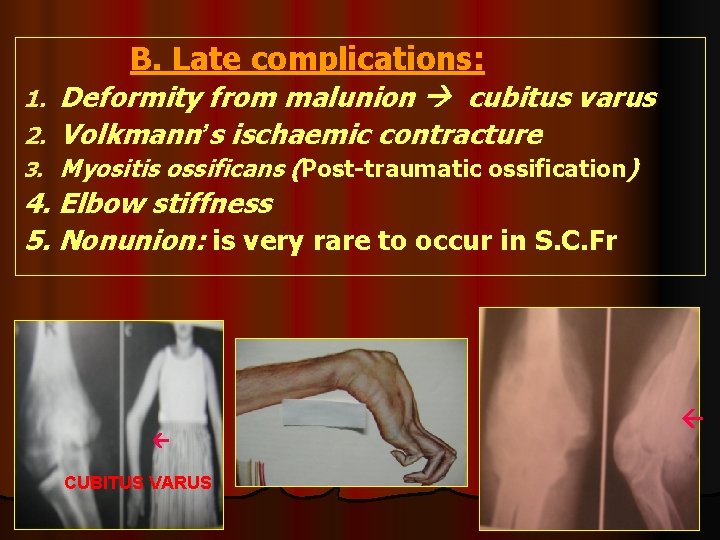

B. Late complications: 1. 2. Deformity from malunion cubitus varus Volkmann’s ischaemic contracture 3. Myositis ossificans (Post-traumatic ossification) 4. Elbow stiffness 5. Nonunion: is very rare to occur in S. C. Fr CUBITUS VARUS